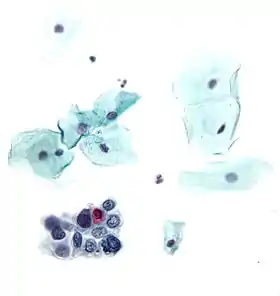

Micrograph of a normal pap smear Micrograph of a Pap test showing a low-grade intraepithelial lesion (LSIL) and benign endocervical mucosa. Pap stain.

Micrograph of a Pap test showing a low-grade intraepithelial lesion (LSIL) and benign endocervical mucosa. Pap stain. Micrograph of a Pap test showing trichomoniasis. Trichomonas organism seen in the upper right. Pap stain.